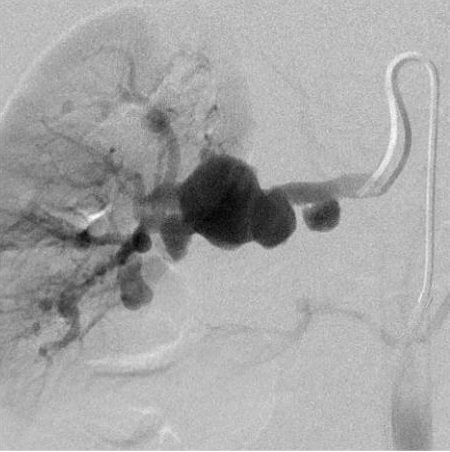

首次报告肾动脉瘤是在1770年,Rouppe 报告了一个海员之死,尸检显示其死于肾的假性动脉瘤破裂[17]。肾动脉瘤可以分为肾实质动脉瘤和肾实质外动脉瘤。以前曾经认为肾动脉瘤是非常罕见的,随着CT,MRI和超声的出现,肾动脉瘤被偶然发现的病例越来越多,并不罕见。

过去30年间,肾动脉及其分支的动脉瘤越来越多地受到关注【1~15】。